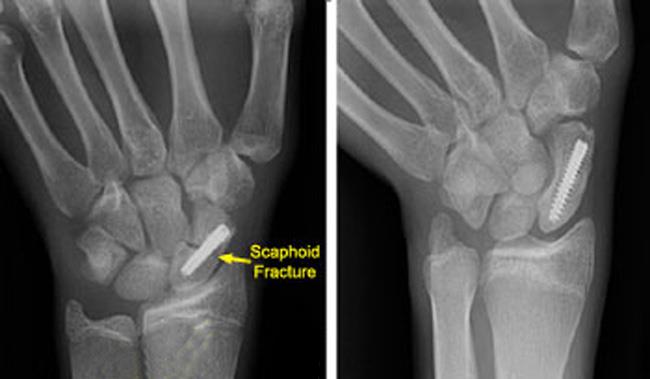

골치아픈 골절이 될 가능성 이 높은 ‘주상골 골절' 입니다. 엄지손가락 뼈와 연결되어 있는 '큰마름뼈' 안쪽에 있는 뼈 입니다.

이 배모양의 뼈가 이야기되는 이유는 생각보다 많은 환자분들이 골절인지 놓치기 쉽기도 하며, 불유합이 되기 쉬운 뼈이기 때문입니다. 손의 골절중에는 가장 흔한 골절로서, 진단이 늦어지면 치료도 늦어지게 됩니다. 즉, 진료를 받지 않는다면 예후가 나빠지는 경우가 많습니다. 따라서, 손목을 삐었는데 좀 심하게 삐엇다 싶으면 무조건 영상의학적 검사(X-ray)를 시행해 보아야 합니다. 특이한 점은 처음 시행한 엑스레이에서 '음성' 이 나왔더라도, 통증이 계속되거나 이 주상골 골절이 의심되는 경우에는 '2주 후'에 엑스레이를 다시 찍어볼 필요가 있습니다.

Herbert B의 경우 전위가 없거나, 최소한의 전위가 있는 경우 경피적 나사고정을 시행해 볼 수 있습니다. 하지만 전위가 있거나 불안정한 경우, 정확한 정복술과 함께 관혈적나사내고정술이 시행되어야 합니다. 내고정 기기로는 K강선이나, Acutrak 나사, Herbert 나사, AO compression screw 등을 사용할 수 있습니다. 관혈적 정복술로는 Waist나 distal 1/3 골절의 경우 Volar approach를, Proximal pole 골절의 경우는 Dorsal approach를 시행할 수 있습니다. (혈관은 손등쪽에 위치하므로 주의하여야 하며 골이식이 필요한 경우에는 Volar approach 를 이용할 수 있습니다.)